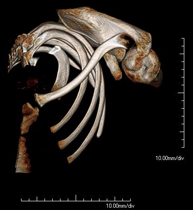

- TC Parrilla costal

Exploración radiológica que mediante un sistema de rayos X y detectores que giran alrededor del paciente, reconstruyendo las imágenes por ordenador, permite el estudio detallado de la parrilla costal.